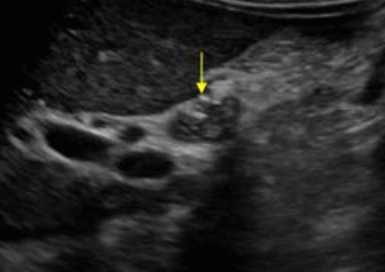

미리찌 증후군 (Mirizzi's syndrom) Mirizzi's syndrom 은 담낭경부, Hartmann's pouch 혹은 담낭관의 결석에 의해 총 간관(CHD)이 폐쇄되는 질환이다. 총 간관(CHD)이 협착되면서 상부담관은 확장되고 하부담관의 직경은 정상으로 나타난다. 증상은 폐쇄성 황달, 복부통증, 발열 등이 나타난다. 급성담낭염이 있으면서 담관폐쇄를 동반할 경우 의심해 볼 수 있다. 담낭절제술 후에 남아있는 담낭관의 결석이 총 간관(CHD)을 직접 누르거나 염증성 협착을 유발하기도 한다.

US finding

- 담낭관 또는 담낭 경부에 결석이 확인된다.

- 총간관(CHD) 또는 담낭관(cystic duct)의 확장소견이 보인다.

- 간내외 담관의 확장이 관찰된다.